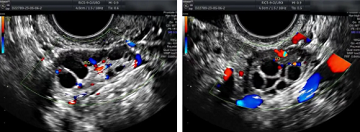

最直接、最直观的诊断是通过阴道B超声检查,可以看到双侧卵巢卵泡的数量、大小和发育。这是基本卵泡检查的最佳方法,既简单又无创。

窦卵泡处于卵泡发育的早期阶段,是成熟卵泡发育的基础。为了估计未来的生育能力,可以评估女性体内剩余的活卵数量。剩余卵泡数量越多,女性怀孕的可能性就越大。相反,卵泡数量较少表明怀孕的机会减少。

02、多少个窦卵泡正常?

正常情况下,女性双侧卵巢的基本卵泡数量分别为5-12个。卵巢中窦卵泡的数量与女性的年龄有关。随着年龄的增长,窦卵泡的数量逐渐减少。

目前普遍认为3-6个窦卵泡计数值较低,表明卵巢储备功能下降。